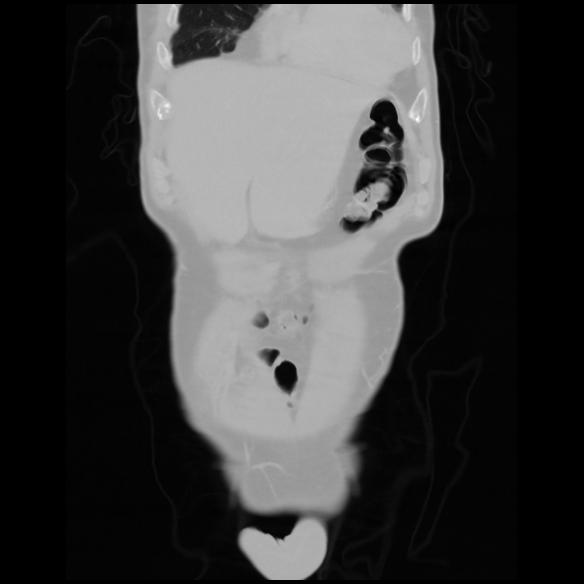

6 CUERPO,CE,Coronal,3.000,CUERPO,Coronal,